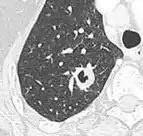

| CT scan of the lung showing bullae in the lower lung lobes of a subject with type alpha-1-antitrypsin deficiency. There is also increased lung density in areas with compression of lung tissue by the bullae. | |